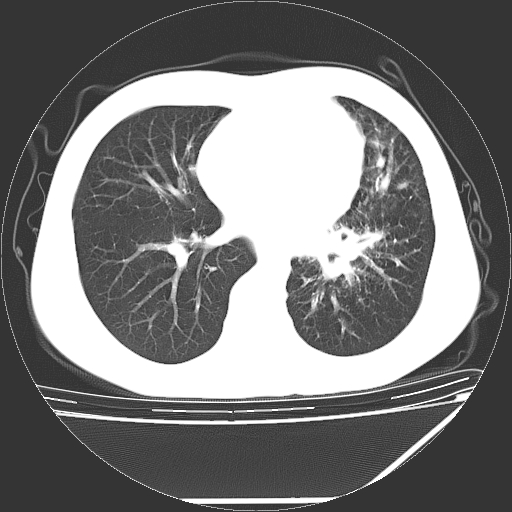

男,13岁,咳嗽、咳痰伴发热一周。

上纵隔课件多枚淋巴结,部分相互融合,左侧支气管壁增厚,肺纹理较右侧增粗,患者,男,13岁,

中上纵隔见多枚淋巴结肿大,部分相互融合成团片,左肺门增大,上叶支气管变窄,肺内多处斑片状 索条状及棉絮状致密影。临床“男,13岁,咳嗽、咳痰伴发热一周。”首先考虑:原发综合征!不除外淋巴瘤可能!

中上纵隔见多枚淋巴结肿大,部分相互融合成团片,左肺门增大,上叶支气管变窄,左肺支气管血管束增粗,可见磨玻璃样影。临床“男,13岁,咳嗽、咳痰伴发热一周。”首先考虑:淋巴瘤可能性大!